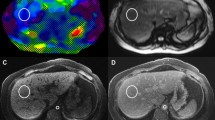

MR elastography

All the participants underwent liver MR examination on a 3-T MR imaging unit (Discovery MR 750; GE Medical Systems, Milwaukee, WI) using an 8-channel phased-array coil and fasted for at least 6 h before the examination. An active pneumatic driver was located outside the imaging room and produced 60-Hz mechanical vibrations. The active driver was connected with a passive driver through a plastic tube to deliver the vibrations to the right upper abdomen. As the patient stayed in the supine position, the passive driver was attached to the right chest wall via a rubber belt and the center of the driver was to be located at the xiphisternum level. Image acquisition of MRE was performed with a two-dimensional spin-echo echo-planar imaging (SE-EPI) sequence and the imaging parameters were as follows: TR/TE, 600/58 ms; flip angle, 30°; matrix, 256 × 128; bandwidth, 250 Hz/pixel; imaging frequency, 64 MHz; field of view, 42 × 42 cm; parallel imaging acceleration factor, 2; section thickness/ intersection gap, 10/0 mm; slice number, 3; number of excitations, 2; and acquisition time, 19 s. Three slices were acquired at the widest part of the liver. The liver stiffness maps were generated by processing the acquired propagating shear wave image through an inversion algorithm [1, 12]. For each participant, two radiologists independently measured the liver stiffness (LSM-MRE) values by placing ROIs in the right lobe of the liver on the stiffness maps. As a rule, each ROI was at least 150 mm2 and was positioned away from blood vessels, marginal liver tissues, poor shear wave amplitude, and multi-path wave interference. LSM-MRE value was expressed in kilopascals (kPa).

Figure 2 shows MRE, DWI (b = 0 s/mm2) images and ADC, Dt, Dp, as well as f maps for a patient with fibrosis stage 3 and inflammatory activity grade 2.